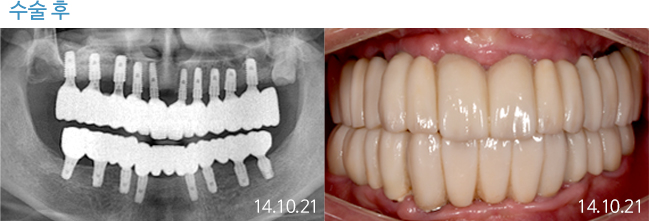

한 번 잘 심으면 10년 뒤에도 끄떡없는

더와이즈 임플란트

첨단 장비를 이용한 정확한 진단, 안정성이 입증된 정품 재료 사용,

노하우가 풍부한 숙련된 의료진의 시술 등이 임플란트 수명을 결정합니다.

※ 실제 본원에서 치료 받은 환자의 동의를 얻어 게재했습니다.

개인의 특성에 따라 부작용이 발생할 수 있으므로 담당의와 충분히 상의하시길 바랍니다.

THEWISE 치료별 전후사진